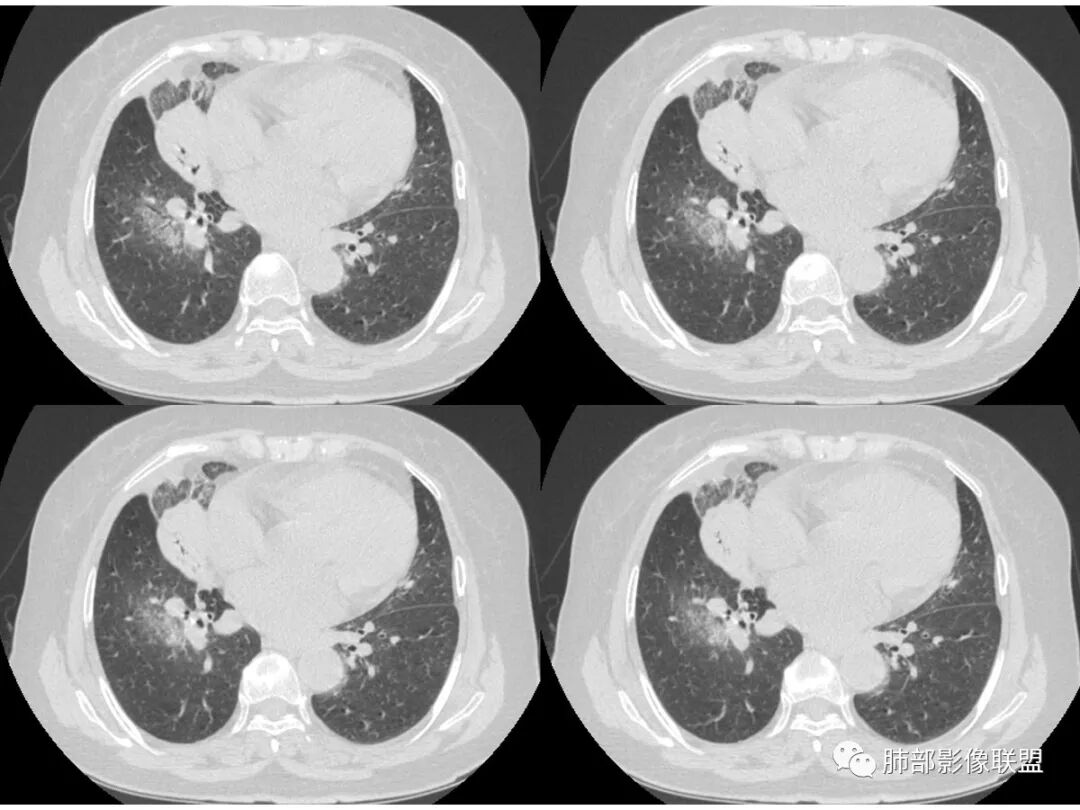

胸CT:右肺上叶实变内可见支气管充气征,近端支气管狭窄,远端扩张,周围可见毛玻璃影,右肺中叶支气管闭塞,并可见气道壁钙化,右肺中叶体积缩小,实变内可见空洞,并可见气液平面,空洞周围可见毛玻璃样影,右肺下叶支气管开口狭窄,右肺门淋巴结肿大。纵隔窗可见病灶与壁层胸膜间隙增宽,考虑良性病变-----感染性病变------TB?

老年女性,慢性病程,咳嗽伴白色粘液痰,无发热腹痛,糖尿病,白细胞及C反应蛋白不高,血沉快,铁蛋白高。胸部CT,右肺上叶大片状实变伴磨玻璃密度影,边界不清,边缘局部膨隆,叶裂弧形下坠,实变影宽基底与胸膜相贴;右肺下叶前基底段见类似病灶;右肺中叶不张并空洞形成,空洞内见气液平面;综合考虑右肺上叶及下叶肺炎型肺癌,右肺中叶结核。

这里是中叶的不张和空洞,有钙化,结核确实也不能排除

主病灶应该是粘腺腺癌,右中叶不张?,内空洞,壁光滑,考虑感染

2.南大理论:粘液腺癌起源于外周,所以主体病灶位于胸膜下多见,这个病人主体病灶位于中心,外周磨玻璃为主,部分磨玻璃模糊

3.熊老师告诉我们:肺结核可以有磨玻璃,这个我以前一直不知道,右肺门淋巴结有钙化,病灶内纵膈窗隐约细细点状钙化,所以结核磨玻璃可以,

中叶的体积缩小,也不是粘液腺癌能完全解释,